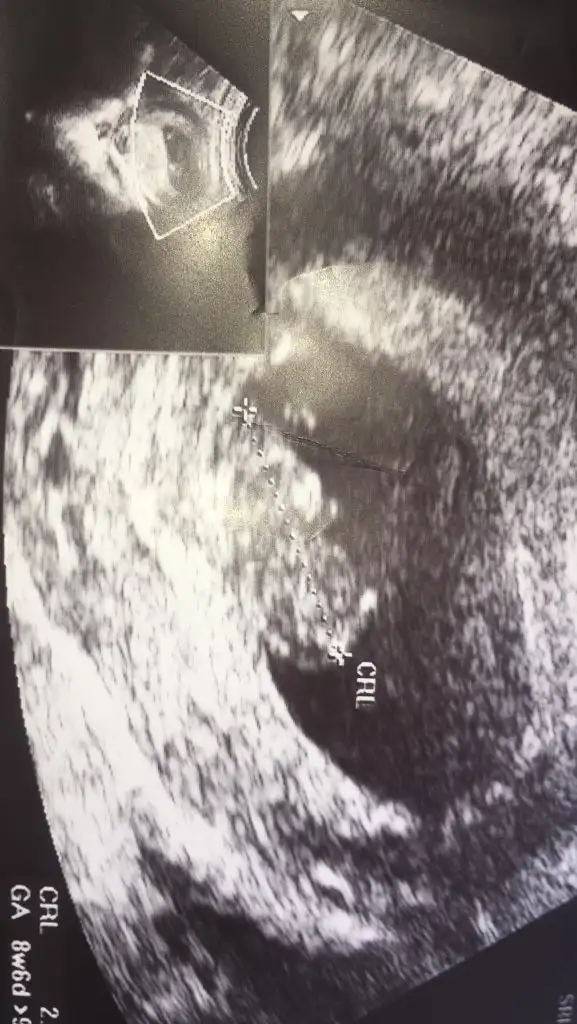

Bak şimdi kız mı erkek mi ay Allah sen iyice şaşırttın beni

Karından ise erkek yazdım vajinal ise kız yazmıştım siz vajinal dediniz o zaman kız diyorum teoriye göre onu yazmak istemiştim

Diğer üç resim karından siz bir resime bakarak kız dediniz zaten 16 haftada gidicem zaten kesinleşir sen karından dediğine göre erkek bir resim kız dedin

Diğer üç resim karından siz bir resime bakarak kız dediniz zaten 16 haftada gidicem zaten kesinleşir sen karından dediğine göre erkek